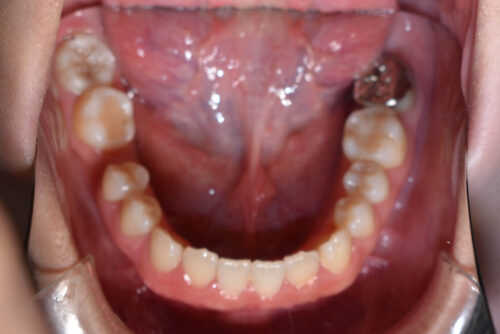

初診時年齢 28歳 女性

歯のでこぼこ(叢生)

下顎右側第一大臼歯欠損(歯をぬいた)

本症例も

下顎右側第一大臼歯欠損

上下とも歯が唇側に傾斜し

下の歯が上の歯よりも外にでている 受け口の状態でした。

非抜歯矯正治療計画で

下顎は

ご自身の歯で かめるように

歯の欠損部は

全てスペースを閉じる

非抜歯矯正治療を開始しました。

ワイヤー8か月後です。

本症例のように

歯科矯正用アンカースクリュー(デュアル・トップオートスクリュー)を利用し

下顎の後方移動を行うことで

歯を抜かない非抜歯矯正治療でも

受け口を整えることができます。